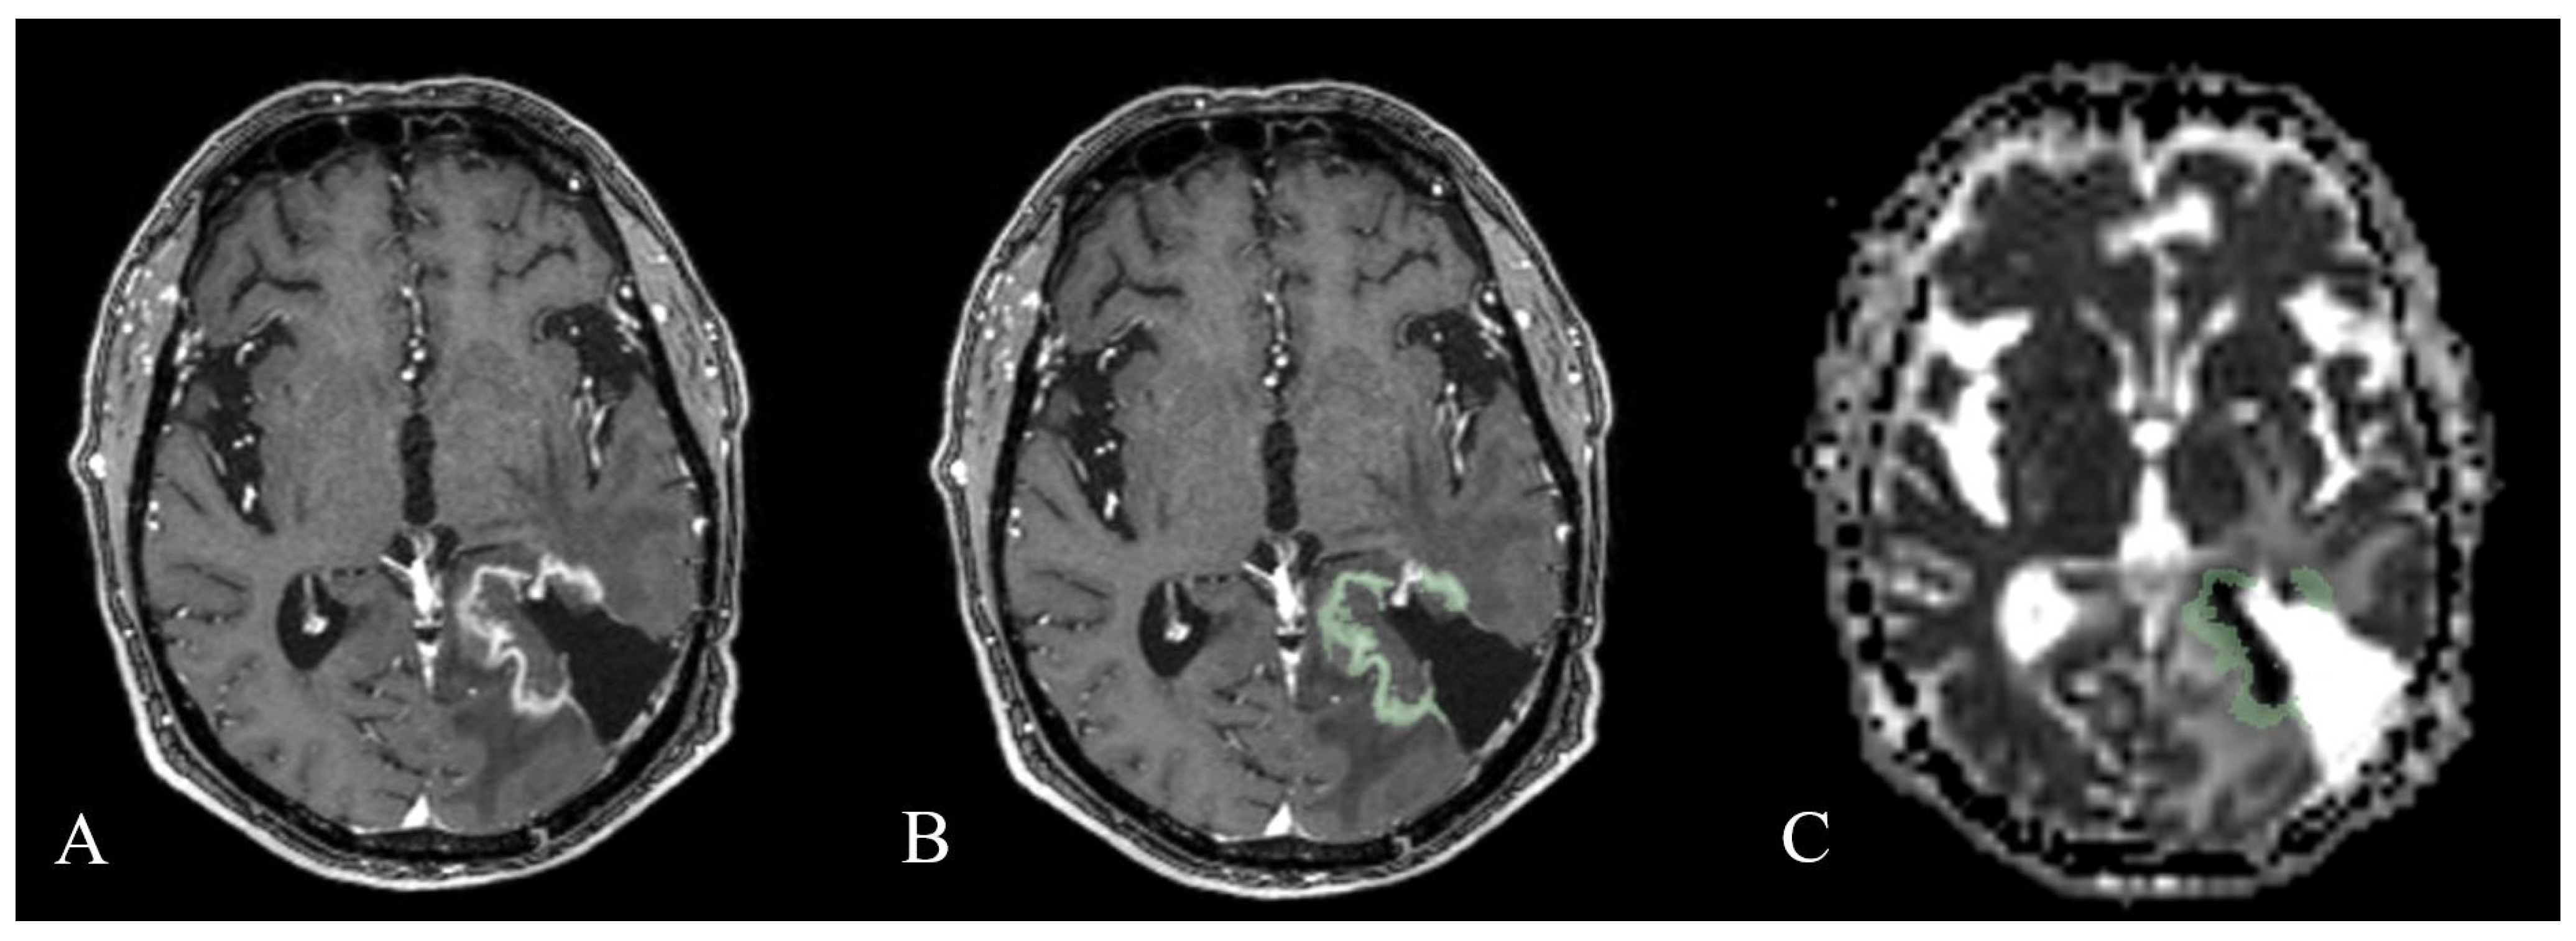

2.3. Image Analysis